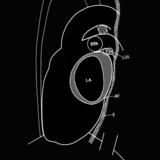

Left atrial enlargement

Date: 11/21/2006

Views: 2317

Views: 2373